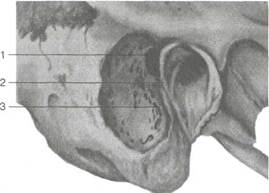

Рис. 5.37. Мастоидит. Субперио-стальный абсцесс.

Прорыв гноя через кортикальный слой на наружную поверхность сосцевидного отростка приводит к формированию субпериостального абсцесса. Предшествующие ему припухлость и пастозность кожи в заушной области, сглаженность заушной складки и оттопыренность ушной раковины при этом усиливаются.